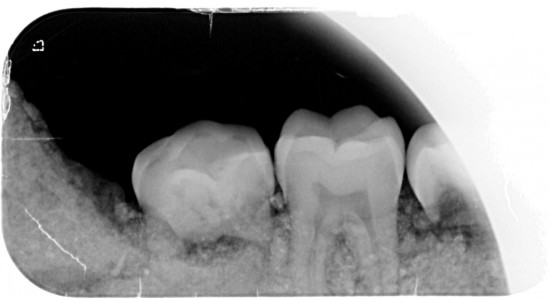

Dit kaakje werd door mijn tandarts grondig bekeken en róntgen foto,s van gemaakt .

Met zijn  langdurige ervaring  uit zijn eigen praktijk. Kunnen namelijk  Molaren verkeerd om zitten. (zie 1ste  molaar linker kaak)

Tevens kunnen er zowel  tanden teveel of te weinig voorkomen .( zie 5 snijtanden ) . De 5de premulaar en hoektand lijken maar een  tand  te zijn , zie rechterkaak. Rontgenfoto wijst echter uit dat het toch 2 aparte tanden zijn .